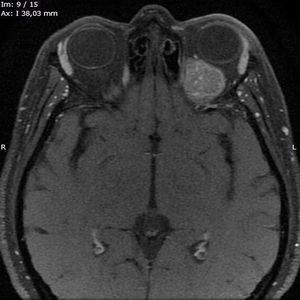

The primary melanoma in this patient was located on the left malleolus of the left ankle which was already resected when the team first met the patient. Melanoma is a type of skin cancer, the primary cause of melanoma is ultraviolet light (UV) exposure in those with low levels of skin pigment. Occurs when skin cells that make the pigment (coloring) called melanin grow out of control and form a tumor. The first sign of melanoma is a change in the size, shape, color, or feel of a mole, and you've probably heard of the ABCDE when it come to diagnosing and classifying melanomas (Asymmetry, Borders, Color, Diameter and Evolution). Although melanoma is a skin cancer, primary malignant extra-cutaneous melanoma (a melanoma that doesn't start on skin) do occur but are very rare, the majority of cases happen when a cutaneous melanoma spreads (metastasizes) throughout the body to its favorite locations such as bone, lung, or just behind the orbit like in this patient. Stay tuned for the surgical resection of the melanoma in this patient on the next post! Case sent by @rpaglioli